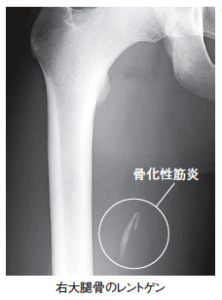

【葛飾区金町のやぎはし整体院】骨化性筋炎(異所性骨化)